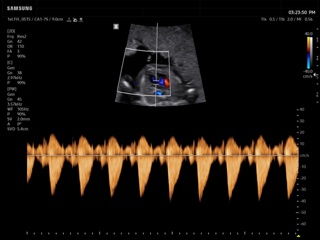

Atlas of ultrasound images - obsterics

In the section "Оbsterics" of atlas the results of ultrasonic examinations of pregnant women with different durations of gestation are represented. Here you can see images of internally organs, cerebrum, cordis and the sex of the fetus, the sonograms of multiple pregnancy, the blood flow in placenta and umbilical cord, defects of fetal`s development, etc.